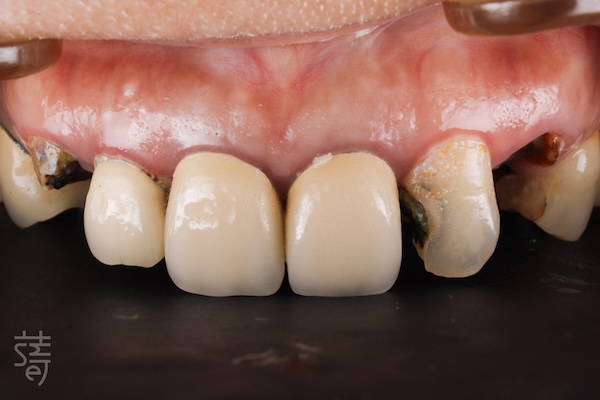

像許多曾被看牙經驗嚇到的病患一樣,陳太太長年對牙科懷有深深恐懼。牙齒出問題時,她總是一拖再拖,直到疼痛難忍才走進診間。當她來到蒔美牙醫諮詢全口植牙重建時,口腔狀況已相當複雜:多顆缺牙、大範圍蛀牙、根尖發炎、牙齒斷裂與舊假牙不密合,疼痛成了生活的一部分,吃飯也變得困難。更讓她難受的是笑容的流失,不再敢自在開口說話。

Like many patients who have been traumatized by dental experiences, Mrs. Chen had lived with a deep fear of the dentist for years. Every time a tooth caused pain, she would put off treatment until it became unbearable. When she finally came to Smile Dental for a consultation about full-mouth reconstruction, her oral condition was quite complex: multiple missing teeth, widespread cavities, root inflammation, fractured teeth, and ill-fitting old crowns. Pain had become a daily burden, and eating was a constant struggle. Even more disheartening, she had lost the confidence to smile freely or speak without hesitation.

第四階段 全瓷美學,重現自然笑容

Stage Four: All-ceramic artistry — restoring a natural smile

植牙完成後,臨時假牙逐步更換為全瓷牙套。

紀醫師與蒔美數位牙技中心協作,精準微調牙色、形態與笑容曲線。全瓷材質呈現真牙般透明感與光澤,燈光下依舊自然。

每個階段間保留足夠癒合與觀察時間,骨與牙齦穩定生長。最終完成的全瓷牙冠在外觀與功能上達到完美平衡,笑容柔和流暢,自然、自信重現。

After the implants healed, temporary restorations were gradually replaced with custom all-ceramic crowns.

Working closely with the Smile Digital Dental Center, Dr. Chi fine-tuned each detail—from tooth shade to contour and smile line. The all-ceramic material reflected light like natural enamel, giving the teeth a lifelike translucency under any lighting.

Each stage allowed ample time for healing and adjustment, ensuring the bone and gums integrated stably. The final result achieved a seamless harmony between aesthetics and function—a soft, confident smile that felt entirely her own.